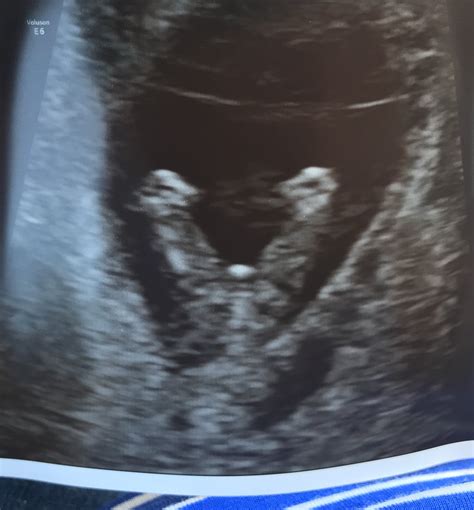

• Baby’s Anatomy: The technician will check for the presence of all major organs and structures.

Anatomy The technician will check for the presence of all major organs, including the brain, heart, stomach, and kidneys.

The technician will look for several key features, including: